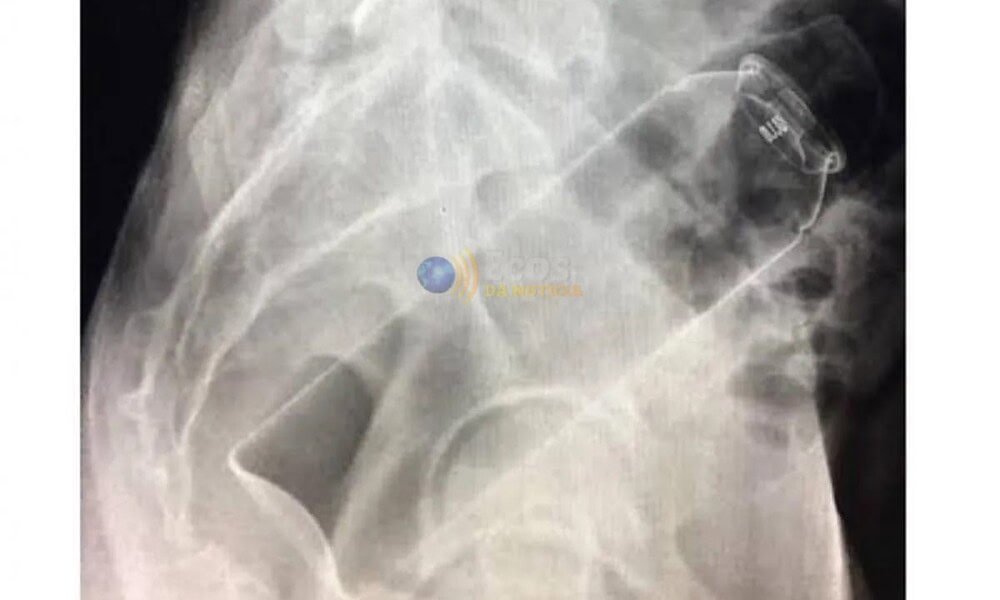

Segundo informações apuradas, o homem teria introduzido o frasco no ânus por conta própria, mas o objeto acabou ficando preso, impossibilitando sua retirada. Desesperado, ele entrou em seu carro, um Volkswagen Virtus, e dirigiu até um hospital particular em busca de atendimento.

No local, a equipe médica realizou um procedimento para remover o desodorante, que foi concluído com sucesso. O empresário permaneceu em observação por algumas horas e recebeu alta ainda durante a madrugada, após avaliação dos profissionais de saúde.